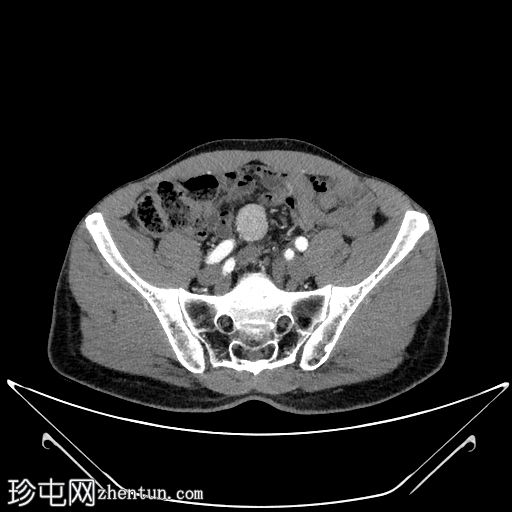

CT扫描

1.jpg

轴向

非造影

边界清晰,单发,均匀强化,实性,无坏死,盆腔内肠系膜肿块病变。

无可疑区域淋巴结肿大,无相关钙化,亦无其他强化间叶病变。

周围结构未见明确侵犯。

下腔静脉扩张至3.6 cm,意义不明。